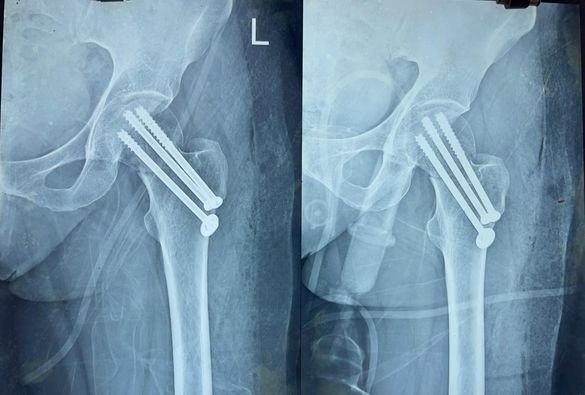

Most neck of femur fractures are treated with partial or total jointreplacement surgeries. however doing so limits active lifestyle in younger individuals. Especially in the Indian system of living. that is why it’s important to take such fractures as surgical emergencies in young people like this 43 year old woman and treat them with screw fixation preferably withing 6 hours of the injury.

This particular patient’s fracture has healed completely and her movements are normal and painless at 7th month, she can now offer Namaz according to her custom. Something that is impossible after a total or partial hipreplacement.